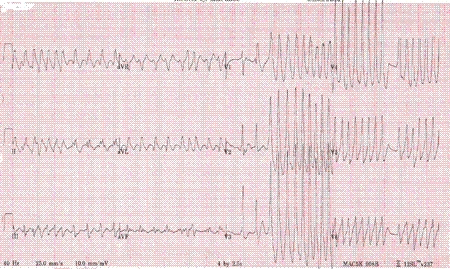

O ECG clássico mostra o intervalo PR encurtado e onda delta no complexo QRS, podendo degenerar em FA.

[Figure caption and citation for the preceding image starts]: Fibrilação atrial com síndrome de Wolff-Parkinson-WhiteDo acervo de Arti N. Shah e Bharat K. Kantharia [Citation ends].

Um estudo eletrofisiológico visando o procedimento de ablação curativa é sugerido para pacientes com alterações no ECG sugestivas de síndrome de Wolff-Parkinson-White que apresentem FA e frequência ventricular rápida.